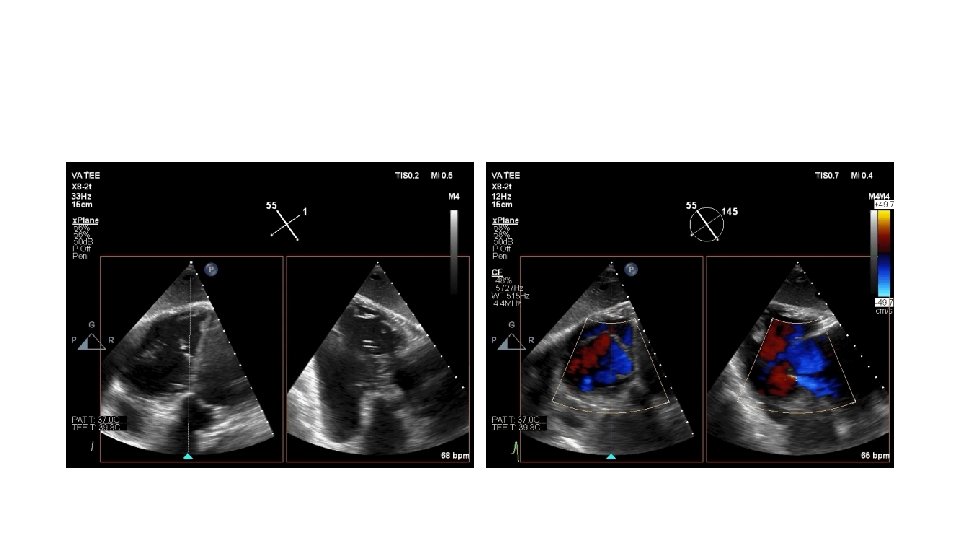

80 yo male with mild dementia referred for evaluation of Progressive dyspnea >1 year Exam: venous distention, TR murmur, no RV lift Creat 2. 2 Transthoracic Echo: Isolated severe TR. IVC 3. 3 cm. RA is dilated RV normal function. Dilated annulus (4. 2 cm)-presumed mechanism of TR. TEE, right heart catheterization RAP 16, and coronary angiography: non obstr CAD What do you do next? Medical management, Refer to CV surgery , other options

Tricuspid Valve (TV) Imaging • TV imaging is challenging • Three TV leaflets (anterior, septal and posterior) are thin and membranous Huitin et al. Archives of Cardiovascular Diseases Volume 109, Issue 1, January 2016, Pages 67 -80

• TV assessment • severity of TR • Mechanism of • mode of leaflet coaptation, • degree of tricuspid annulus enlargement and tenting • TAPSE • 3 D-TEE • Cardiac CT • cardiac MRI